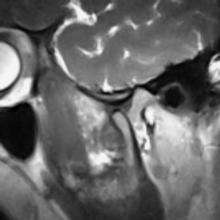

The temporomandibular joints are the dual articulation of the mandible with the skull. Each TMJ is classed as a "ginglymoarthrodial" joint since it is both a ginglymus (hinging joint) and an arthrodial (sliding) joint,[40] and involves the condylar process of the mandible below, and the articular fossa (or glenoid fossa) of the temporal bone above. Between these articular surfaces is the articular disc (or meniscus), which is a biconcave, transversely oval disc composed of dense fibrous connective tissue. Each TMJ is covered by a fibrous capsule. There are tight fibers connecting the mandible to the disc, and loose fibers which connect the disc to the temporal bone, meaning there are in effect 2 joint capsules, creating an upper joint space and a lower joint space, with the articular disc in between. The synovial membrane of the TMJ lines the inside of the fibrous capsule apart from the articular surfaces and the disc. This membrane secretes synovial fluid, which is both a lubricant to fill the joint spaces, and a means to convey nutrients to the tissues inside the joint. Behind the disc is loose vascular tissue termed the "bilaminar region" which serves as a posterior attachment for the disc and also fills with blood to fill the space created when the head of the condyle translates down the articular eminence.[41] Due to its concave shape, sometimes the articular disc is described as having an anterior band, intermediate zone and a posterior band.[42] When the mouth is opened, the initial movement of the mandibular condyle is rotational, and this involves mainly the lower joint space, and when the mouth is opened further, the movement of the condyle is translational, involving mainly the upper joint space.[43] This translation movement is achieved by the condylar head sliding down the articular eminence, which constitutes the front border of the articular fossa.[34] The function of the articular eminence is to limit the forwards movement of the condyle.[34] The ligament directly associated with the TMJ is the temporomandibular ligament, also termed the lateral ligament, which really is a thickening of the lateral aspect of the fibrous capsule.[34] The stylomandibular ligament and the sphenomandibular ligament are not directly associated with the joint capsule. Together, these ligaments act to restrict the extreme movements of the joint.[44]

Noises from the TMJs are a symptom of dysfunction of these joints. The sounds commonly produced by TMD are usually described as a "click" or a "pop" when a single sound is heard and as "crepitation" or "crepitus" when there are multiple, grating, rough sounds. Most joint sounds are due to internal derangement of the joint, which is a term used to describe instability or abnormal position of the articular disc.[45] Clicking often accompanies either jaw opening or closing, and usually occurs towards the end of the movement. The noise indicates that the articular disc has suddenly moved to and from a temporarily displaced position (disk displacement with reduction) to allow completion of a phase of movement of the mandible.[5][26] If the disc displaces and does not reduce (move back into position) this may be associated with locking. Clicking alone is not diagnostic of TMD since it is present in high proportion of the general population, mostly in people who have no pain.[5] Crepitus often indicates arthritic changes in the joint, and may occur at any time during mandibular movement, especially lateral movements.[5] Perforation of the disc may also cause crepitus.[34] Due to the proximity of the TMJ to the ear canal, joint noises are perceived to be much louder to the individual than to others. Often people with TMD are surprised that what sounds to them like very loud noises cannot be heard at all by others next to them. However, it is occasionally possible for loud joint noises to be easily heard by others in some cases and this can be a source of embarrassment e.g. when eating in company.